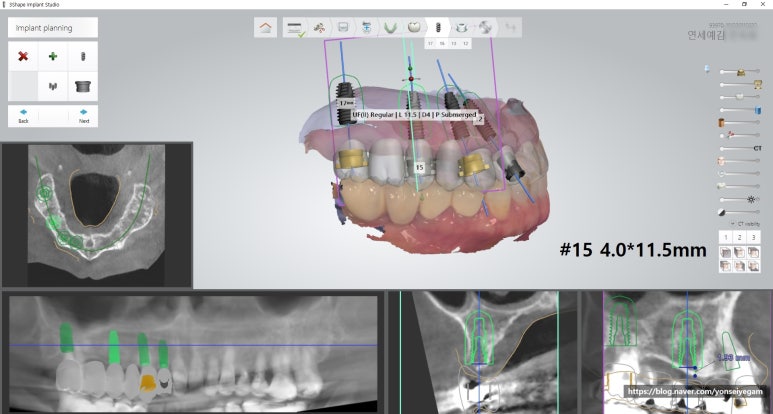

이 브릿지 부분에 총 4개의 임플란트를 심고 머리는 6개를 만드는 방법을 택했습니다.

여러개의 임플란트인데다가, 앞니까지 포함된 임플란트라

정확하고 수술시간이 짧게 하게 위해 네비게이션 임플란트로 수술하기로 결정하였습니다.

1.네비게이션 임플란트의 모의수술을 위해 3D구강스캔, CT를 먼저 촬영하였습니다.

- 이 구강스캔을 바탕으로 임플란트 모의수술이 디자인됩니다.